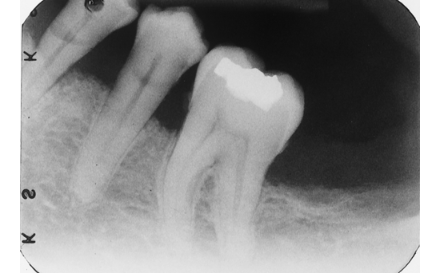

This tooth has a carious lesion, is broken down, and the dentist is contemplating extraction. Which one factor seen here is MOST likely to complicate the extraction?

ankylosis

large carious lesion

short crown length

apical osteosclerosis

What dental anomaly is seen on this image?

external root resorption

internal root resorptions

dens in dente

external root resorption and dens in dente